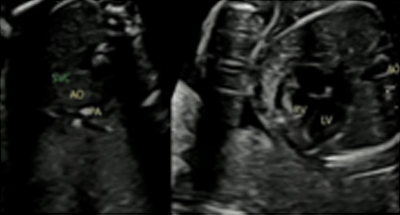

| 20-23ÁÖ | Á¤¹Ð ÃÊÀ½ÆÄ¸¦ ÅëÇÑ Å¾ÆÀÇ Àå±â È®ÀÎ |